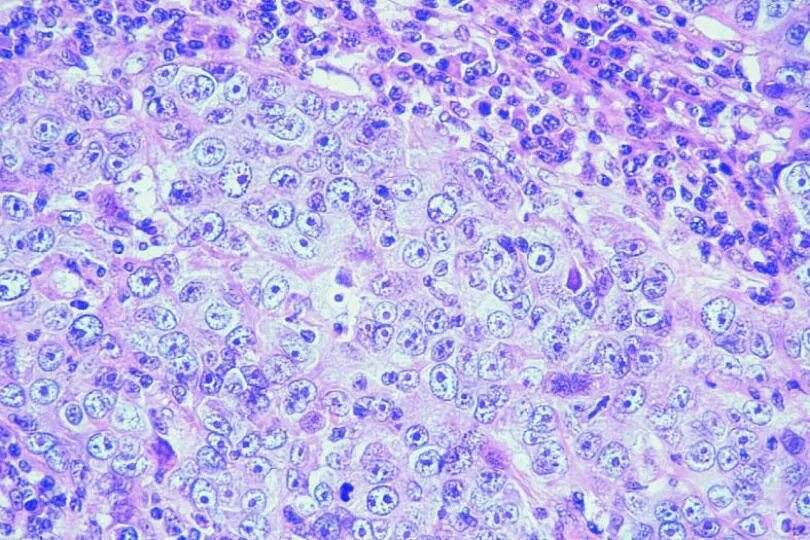

Метастазы щитовидной железы в легкие